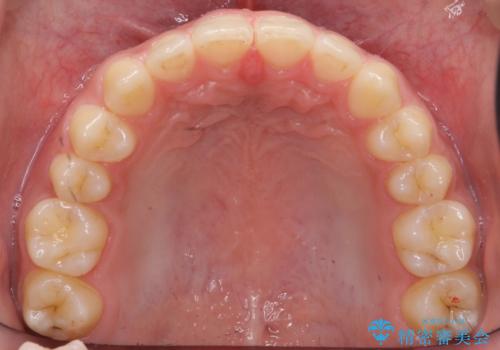

前歯のすきま 受け口 インビザラインで

治療症例の内容

- 治療計画

- 前歯のすき間を気にして来院。

受け口もあり、前歯が端同士であたる、切端咬合となっていました。

下の歯のすき間を閉じて上の歯の内側に入るように位置付けました。

すき間もきれいに閉じ、満足していただきました。

上の前歯は下の歯と直接へりが当たっていた状態(切端咬合)だったため、形がいびつだったのは、わずかにやすりがけをして整えました。

セラミックですき間を閉じようとすると、すきまをうめるために巨大な歯になり、また、下の歯が前に出て強く当たるため、セラミックがかけるおそれがあります。また、下の歯をさけようとすると角度をかえるために歯を極端に削らなければならなくなり、神経をとらなければいけなくなるリスクもあります。

このような歯並びは、セラミックでかぶせるよりは、矯正治療の

適応と言えます。